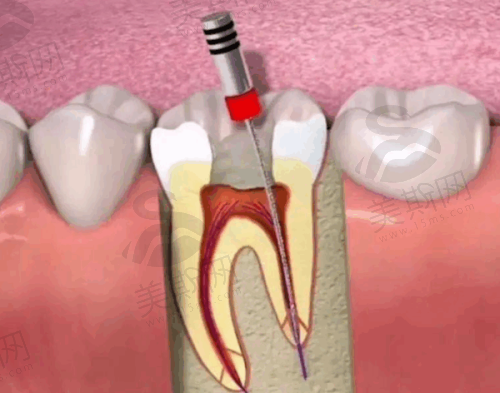

口腔综合诊疗:涵盖补牙(树脂充填、玻璃离子体修复)、拔牙(微创拔除阻生智齿)、根管治疗(显微根管技术提高治愈率)、洗牙(超声波洁牙+喷砂抛光)等基础项目,注重治疗过程的舒适度与精细度。

7. 牙博士口腔集团根管治疗(前牙):980 - 1500元/颗

8. 牙博士口腔集团根管治疗(后牙):1800 - 2800元/颗